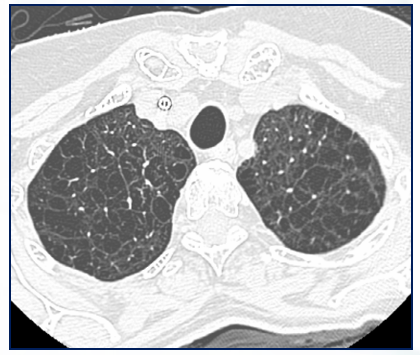

Qual o achado dessa TC de tórax axial?

Destruição e desorganização do parênquima pulmonar, determinando focos de aprisionamento aéreo e redução da atenuação pulmonar (pulmão mais preto).

Enfisema pulmonar

Mais comum nos ápices e segmentos superiores dos pulmões.